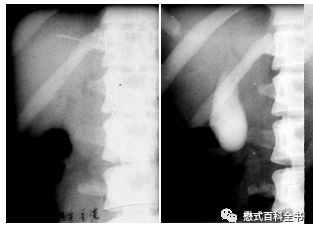

图4:X线胆囊造影(左边造影前、右边造影后)